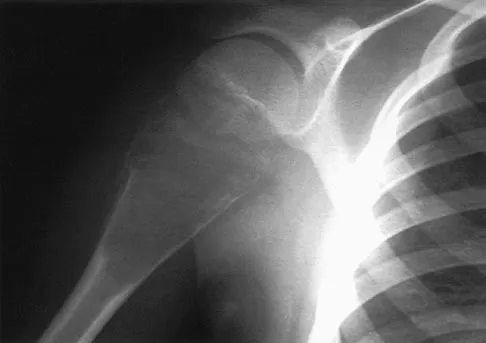

Figure 4a shows the radiograph of a 20-year-old man who has an injury to the right shoulder. Figure 4b shows an arthroscopic view (posterior portal). The arrow points to a

Explanation

The radiograph shows an anterior dislocation of the shoulder. A frequently encountered sequela of this is a compression fracture of the posterolateral humeral head, commonly referred to as a Hill-Sachs defect. The arthroscopic view of the glenohumeral joint visualizes the posterior aspect of the humeral head. In the image, the area devoid of cartilage to the right is the bare area. The indentation seen to the left is a Hill-Sachs defect. Matsen FA, Thomas SC, Rockwood CA, et al: Glenohumeral instability, in Rockwood CA, Matsen FA (eds): The Shoulder, ed 2. Philadelphia, PA, WB Saunders, 1998, pp 611-754.